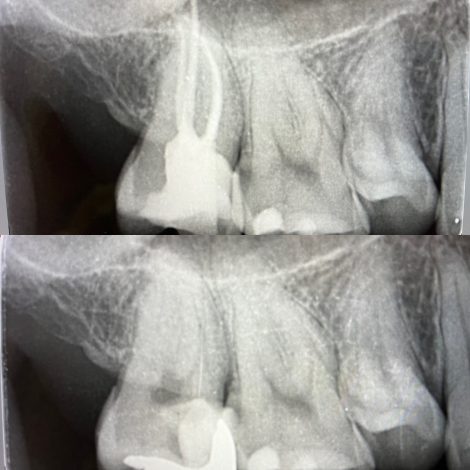

根の治療は複雑です🦷

州デンタルオフィスで行なっている根管治療は、専門医による歯内療法です

歯科用顕微鏡を用いた精密根管治療です🦷

これを、歯内療法のエキスパートが行う✨